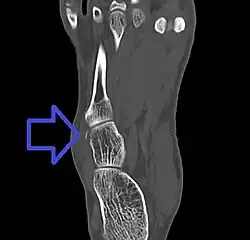

Cuboid fracture

A cuboid fracture is a fracture of the cuboid bone of the foot. Diagnosis is by X-ray imaging, magnetic resonance imaging, or bone scan.[1] Treatment may be conservative or involve surgery, depending on the type of fracture.[1] They are rare.[1]

If the cuboid bone is broken, then it is common for other bones in the foot to be broken or dislocated as well.[2] Cuboid fractures are associated with Lisfranc injuries.[2]